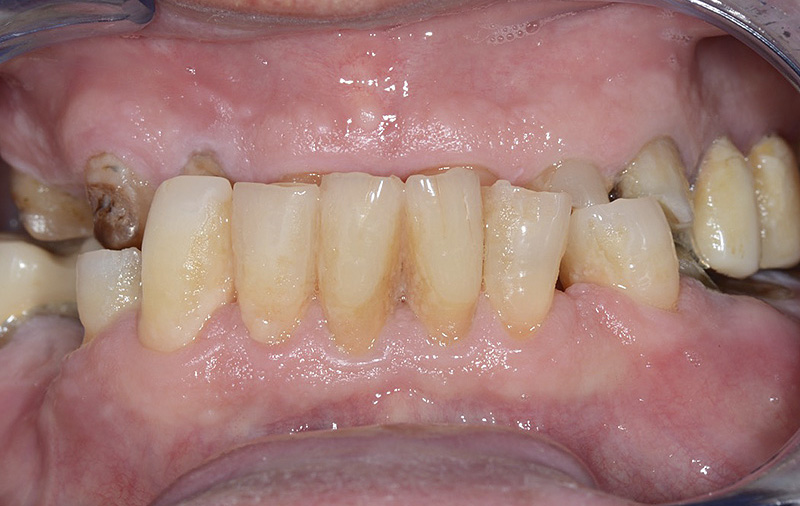

PREMESSA: in seguito all’estrazione dell’incisivo laterale superiore di destra, resasi necessaria per cause batteriche, si decide di affrontare il caso con il posizionamento di un impianto in sostituzione dell’elemento mancante dopo guarigione del sito infetto. Con tecniche rigenerative sia dei tessuti ossei mancanti a causa dell’infezione pregressa, sia dei tessuti gengivali che appaiono inizialmente troppo spostati in alto, si ripristina una corretta morfologia delle parabole (contorni) gengivali e delle papille interdentali (triangoli di gengiva tra due denti vicini).

Vengono utilizzati 2 tipi di provvisori: il primo, cementato ai denti vicini, viene utilizzato dal momento dell’estrazione del dente fino ad impianto osteointegrato (circa 6 mesi); il secondo, avvitato direttamente all’impianto, ha una funzione di prova estetica ma soprattutto di guida per la maturazione dei tessuti gengivali peri-implantari portandoli verso la maturazione completa prima di posizionare la corona finale in disilicato di litio.